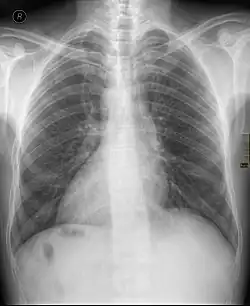

Dekstrokardia

Dekstrokardia (łac. dextrocardia) – medyczne określenie sytuacji, gdy serce znajduje się po prawej stronie klatki piersiowej.

Jeżeli towarzyszy mu nieprawidłowe (po przeciwnych stronach, jakby odbite w lustrze) położenie innych narządów w obrębie klatki piersiowej i jamie brzusznej mówimy o odwróceniu trzewi (łac. situs inversus).